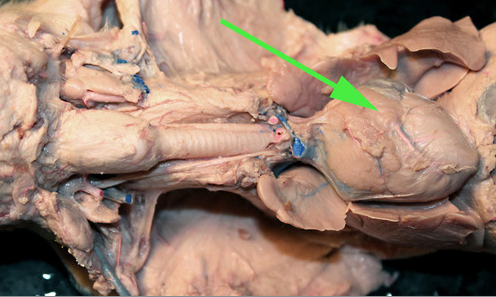

The organ marked by the green arrow arrow is the Spleen

The organ indicated by the green arrow is the SPLEEN